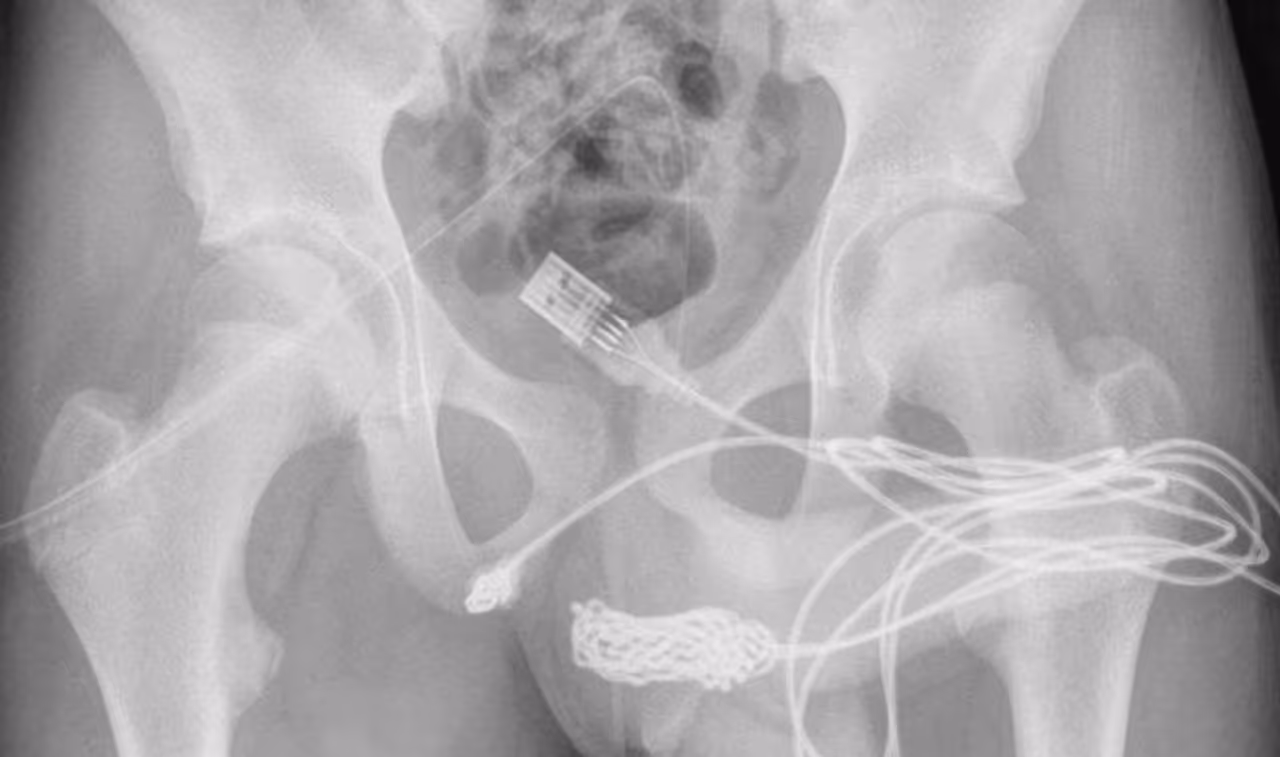

दरअसल, 15 साल का लड़का मोबाइल के यूएसबी केबल से यौन प्रयोग करने की कोशिश कर रहा था। वो अपने पेनिस के अंदर की लंबाई को मापने का प्रयास कर रहा था। मूत्र मार्ग से वो केबल को अंदर डालता गया, डालता गया और फिर अंदर वो गांठ बनती गई। जब वो उसे बाहर निकालने की कोशिश किया तो वो निकला ही नहीं। गांठ बनने की वजह से वो अंदर फंस गया था।

केबल में गांठें और उलझने के साथ, लड़के के पेशाब में खून आने लगा। जब लड़के की मां ने ये देखा तो उसे तुरंत अस्पताल लेकर आई। तब लड़के ने डॉक्टर के सामने कबूल किया कि वो पहले अपनी मां के कमरे से बाहर निकलने का इंतजार किया। इसके बाद उसने अपने अंदर केबल डाली थी। जिसके बाद डॉक्टर ने सर्जरी करके उसे बाहर निकाला। हालांकि डॉक्टर सर्जरी करने में काफी मशक्त करनी पड़ी थी।

फोटो क्रेडिट:Science Direct

नवंबर 2021 में एक यूरोलॉजी केस रिपोर्ट में इसे विचित्र घटना का दस्तावेजीकरण किया गया था। साइंस डायरेक्टर रिपोर्ट में डॉक्टरों ने लिखा,'यूएसबी वायर के दो डिस्टल पोर्ट बाहरी यूरेथ्रल मीटस से निकले हुए पाए गए, जबकि नॉटेड वायर का मध्य भाग मूत्रमार्ग के भीतर बना रहा।' रिपोर्ट में आगे लिखा गया है कि रोगी फिट और स्वस्थ्य किशोर था, जिसका मानसिक स्वास्थ्य विकारों का कोई इतिहास नहीं था।

लिंग के अंदर गांठ बन जाने की वजह से डॉक्टर बिना सर्जरी के इसे निकाल नहीं पा रहे थे। काफी कोशिश के बाद जब वो नहीं निकला तो सर्जरी करनी पड़ी। सर्जरी के बाद लड़का ठीक हो गया और उसे अस्पताल से छुट्टी दे दी गई। हालांकि लंबे वक्त तक उसे डॉक्टर की निगरानी में रहना पड़ा।